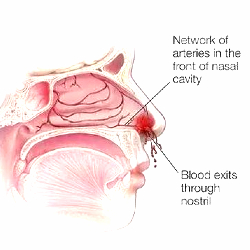

Epistaxis

Epistaxis is bleeding from the nose. The most common causes in children is nose picking, dryness of nose, deviated nasal septam. In adults the most common cause in uncontrolled high blood pressure. Other causes include

- Sinusitis

- Nasal polyps

- Inverted papilloma and

- Sino-nasal tumours / maliqrancy